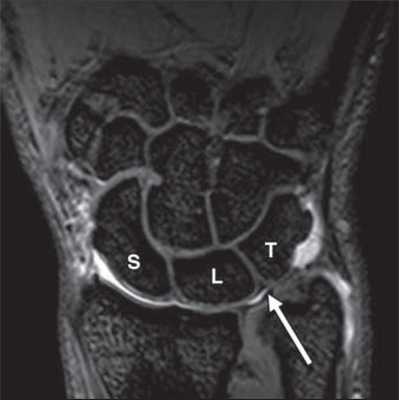

МРТ кисти. Корональная градиентная МРТ. Нормальное изображение полулунно-трехгранной связки. Обозначения: S - ладьевидная кость (scaphoid), L - полулунная кость (lunatum), T- трехгранная кость (triquetrum).